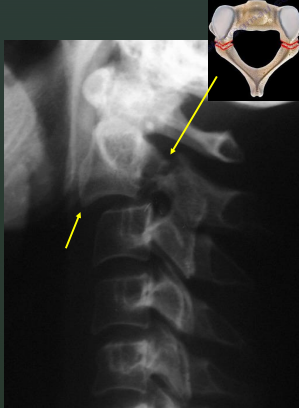

Facets - Unilateral Subluxation

C-spine injury involving flexion, distraction, and rotation resulting in only 1 zygapophyseal joint out of alignment

Spine is not stable, surgery required

A unilateral subluxation of the facet will result in the vertebral body being ____, creating a ____ artifact on the lateral C-spine image.

Rotated

Bowtie

Facets - Bilateral Locks

Extreme flexion and distraction, with both right and left zygapophyseal joints on the same level disrupted created bilateral locked facets

In bilateral facet locks, the affected vertebral body ____ the body immediately inferior.

Jumps over